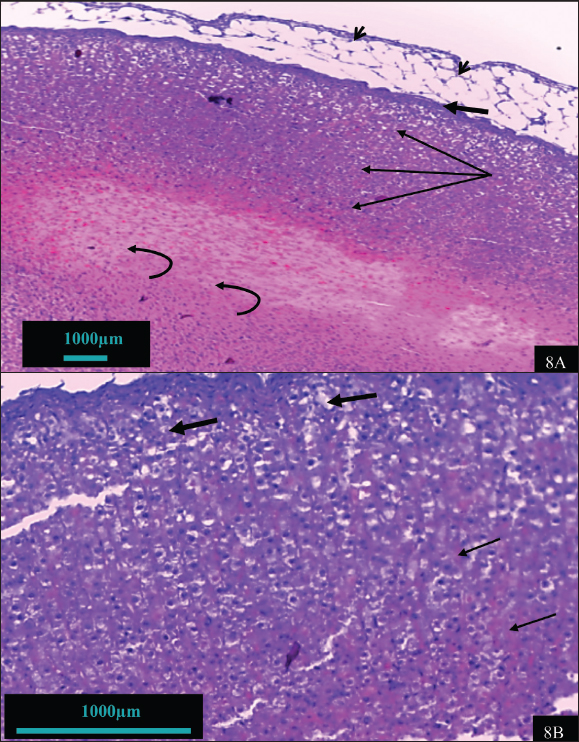

In contrast, the adrenal gland of hypothyroid rats treated with vitamin B12 (hypothyroid + B12) exhibited a notable reparative feature (Fig. 7). Improvements include enhanced capsule integrity, normalization of adrenal cells with clear visible, light-colored nuclei, and restoration of the cellular boundary and cytoplasm. The cell size and number of the cortex and medulla are nearly normal. The features observed in this group are depicted in the control group. The adrenal tissue of rats treated with vitamin B12 exhibited remarkable tissue similarity with the control group (Fig. 8).

Fig. 8. Histomorphohogy of adrenal gland tissues in the vitamin B12 group showing normal capsule (thick arrow), surrounding adipose tissue (arrowhead), normal layers of adrenal cortex (thin arrow), and adrenal medulla (curved arrow) (8A) (100X). The zona glomerulosa cells showed active nuclei (thick arrow), and the cells of the fasciculate layer are arranged in the form of fascicule (thin arrow) (8B) (400X).